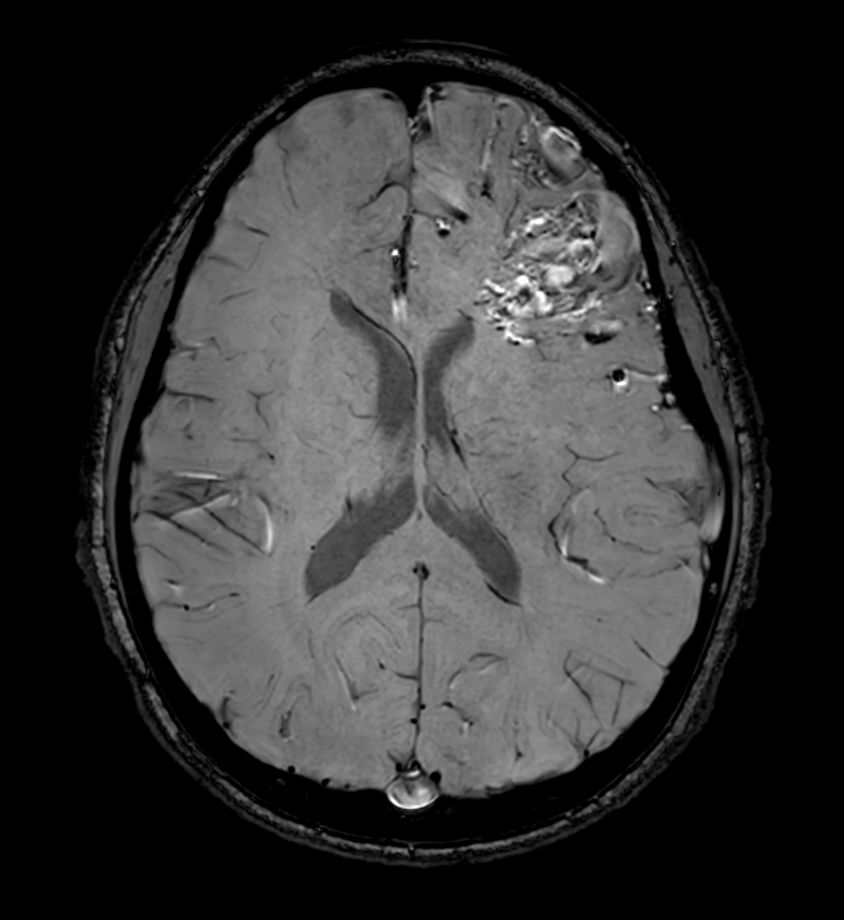

Pediatric brain with AVM

Pediatric patient with frontal brain AVM. MultiVane XD is used to achieve high resolution diagnostic images, even in the case of severe patient motion. SWIp sequence is added to acquire exquisite susceptibility contrast. The 3D sequences with isotropic voxel size enable reformats in any plane without loss of resolution. And 4D-TRAK XD, a fast, dynamic contrast-enhanced MR Angiography method allows to achieve high spatial and temporal resolution simultaneously. Integration of Compressed SENSE acceleration technique enables speeding up of the entire exam.

Axial SWIpCompressed SENSE